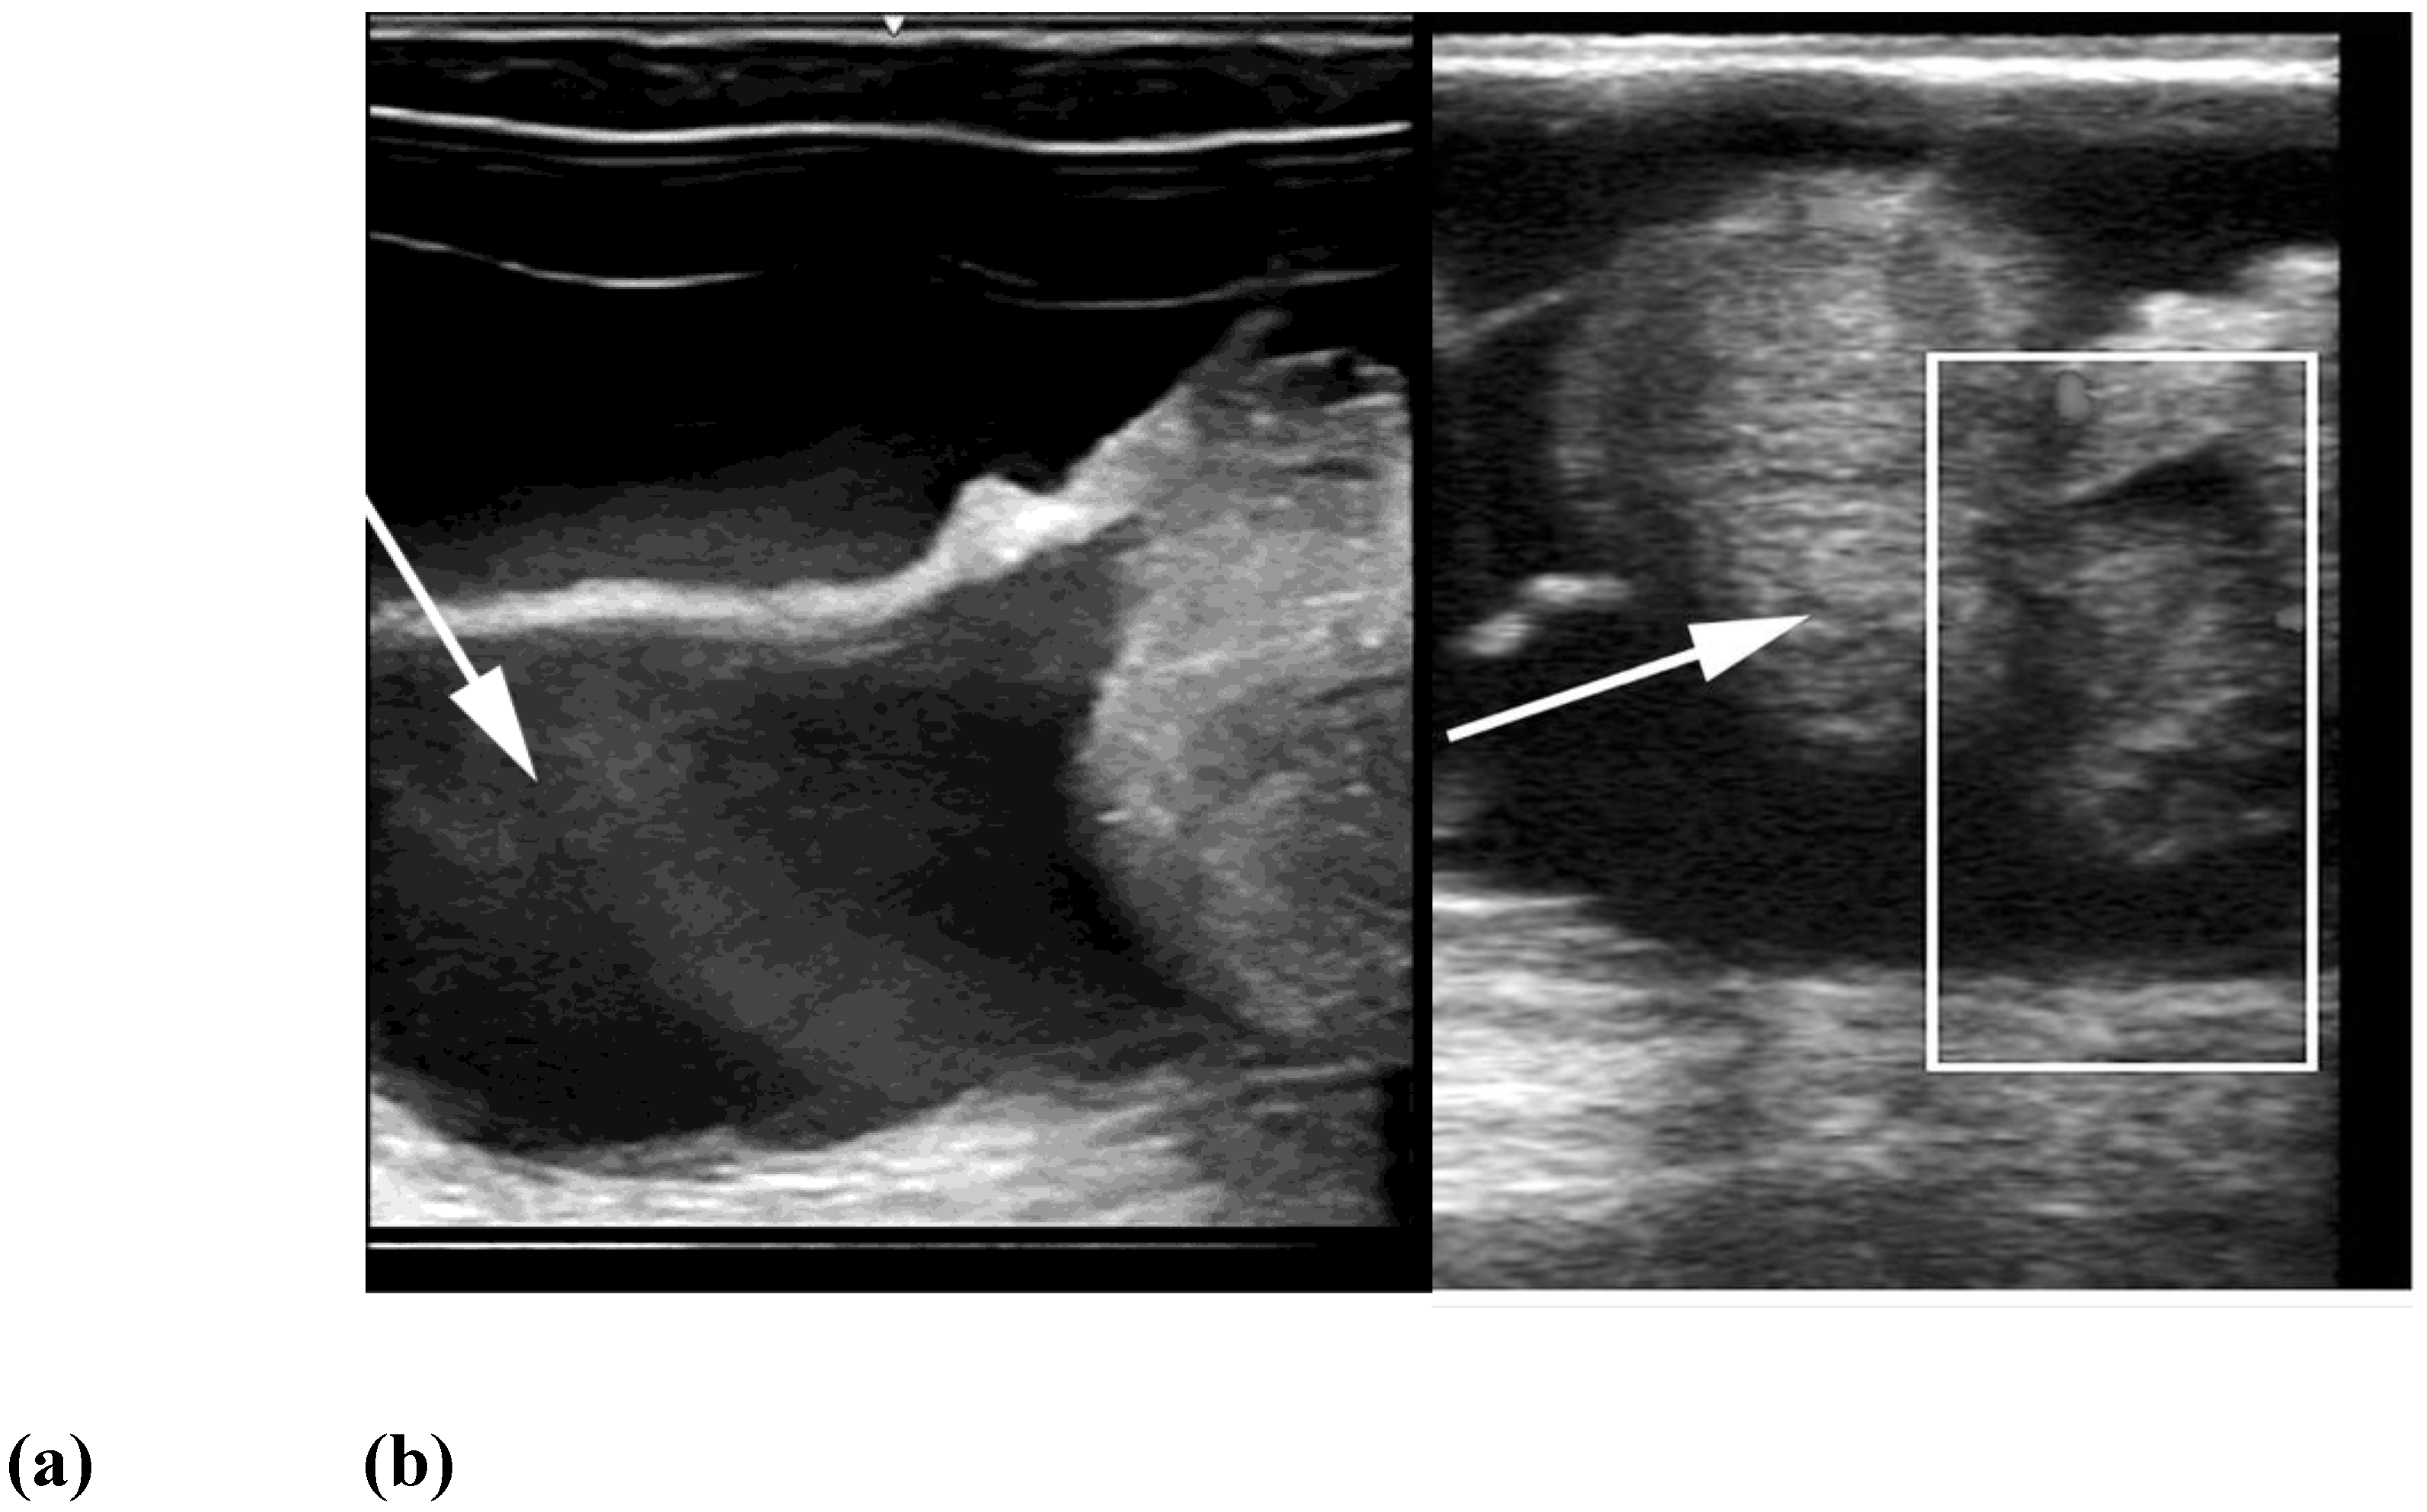

Ovarian dysgenesis/hypoplasia was diagnosed in 36.3% of maiden SACs presented for infertility. This is higher than the 16.8% incidence reported in slaughtered alpacas that were culled for infertility [72]. The high incidence in our data may be due to the inability of referring veterinarians to diagnose these defects. Affected females are generally presented for repeat breeding without evidence of ovulation. In rare cases, the female may be presented due to male rejection in the absence of a pregnancy or a rise in progesterone level [64]. The disorder is characterized by the lack of normal follicular activity, difficulty in visualizing the ovary by ultrasonography, and an infantile reproductive tract [24,87]. Confirmation of the diagnosis is achieved via laparoscopy (Figure 1). Hormonal diagnosis (i.e., serial serum estradiol concentration, anti-mullerian hormone (AMH) concentration) is possible but rarely performed. The ovaries are extremely small, measuring 2 to 3 mm in length. Histologically, this syndrome can be categorized as ovarian hypoplasia (i.e., germ cell deficiency or low germ cell resistance), ovarian dysgenesis (i.e., defective embryonic development of the gonad), or ovarian dysplasia (i.e., abnormal follicular development) [24].

Figure 1. (a) Reproductive tract (scale bar: 1cm) and (b) laparoscopic view of an alpaca with ovarian dysgenesis. Arrows indicate ovaries; (c) Histology of ovarian hypoplasia in an alpaca (scale bar: 2mm).